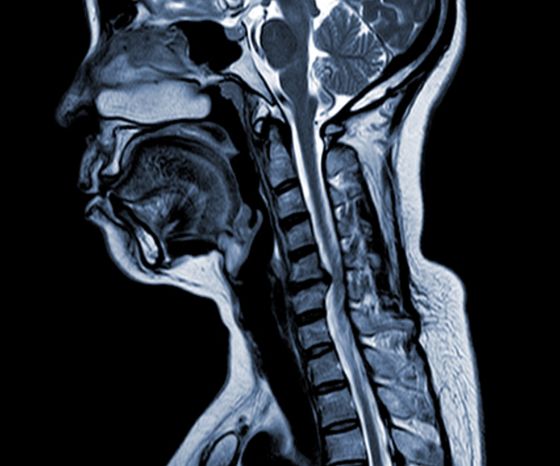

Шейная спондилотическая миелопатия (ШСМ)

• Ключевыми факторами являются дегенерация диска, субпериостальное костеобразование, окостенение задней продольной связки и гипертрофия ligamentum flavum, что приводит к компрессии и сужению позвоночного канала.